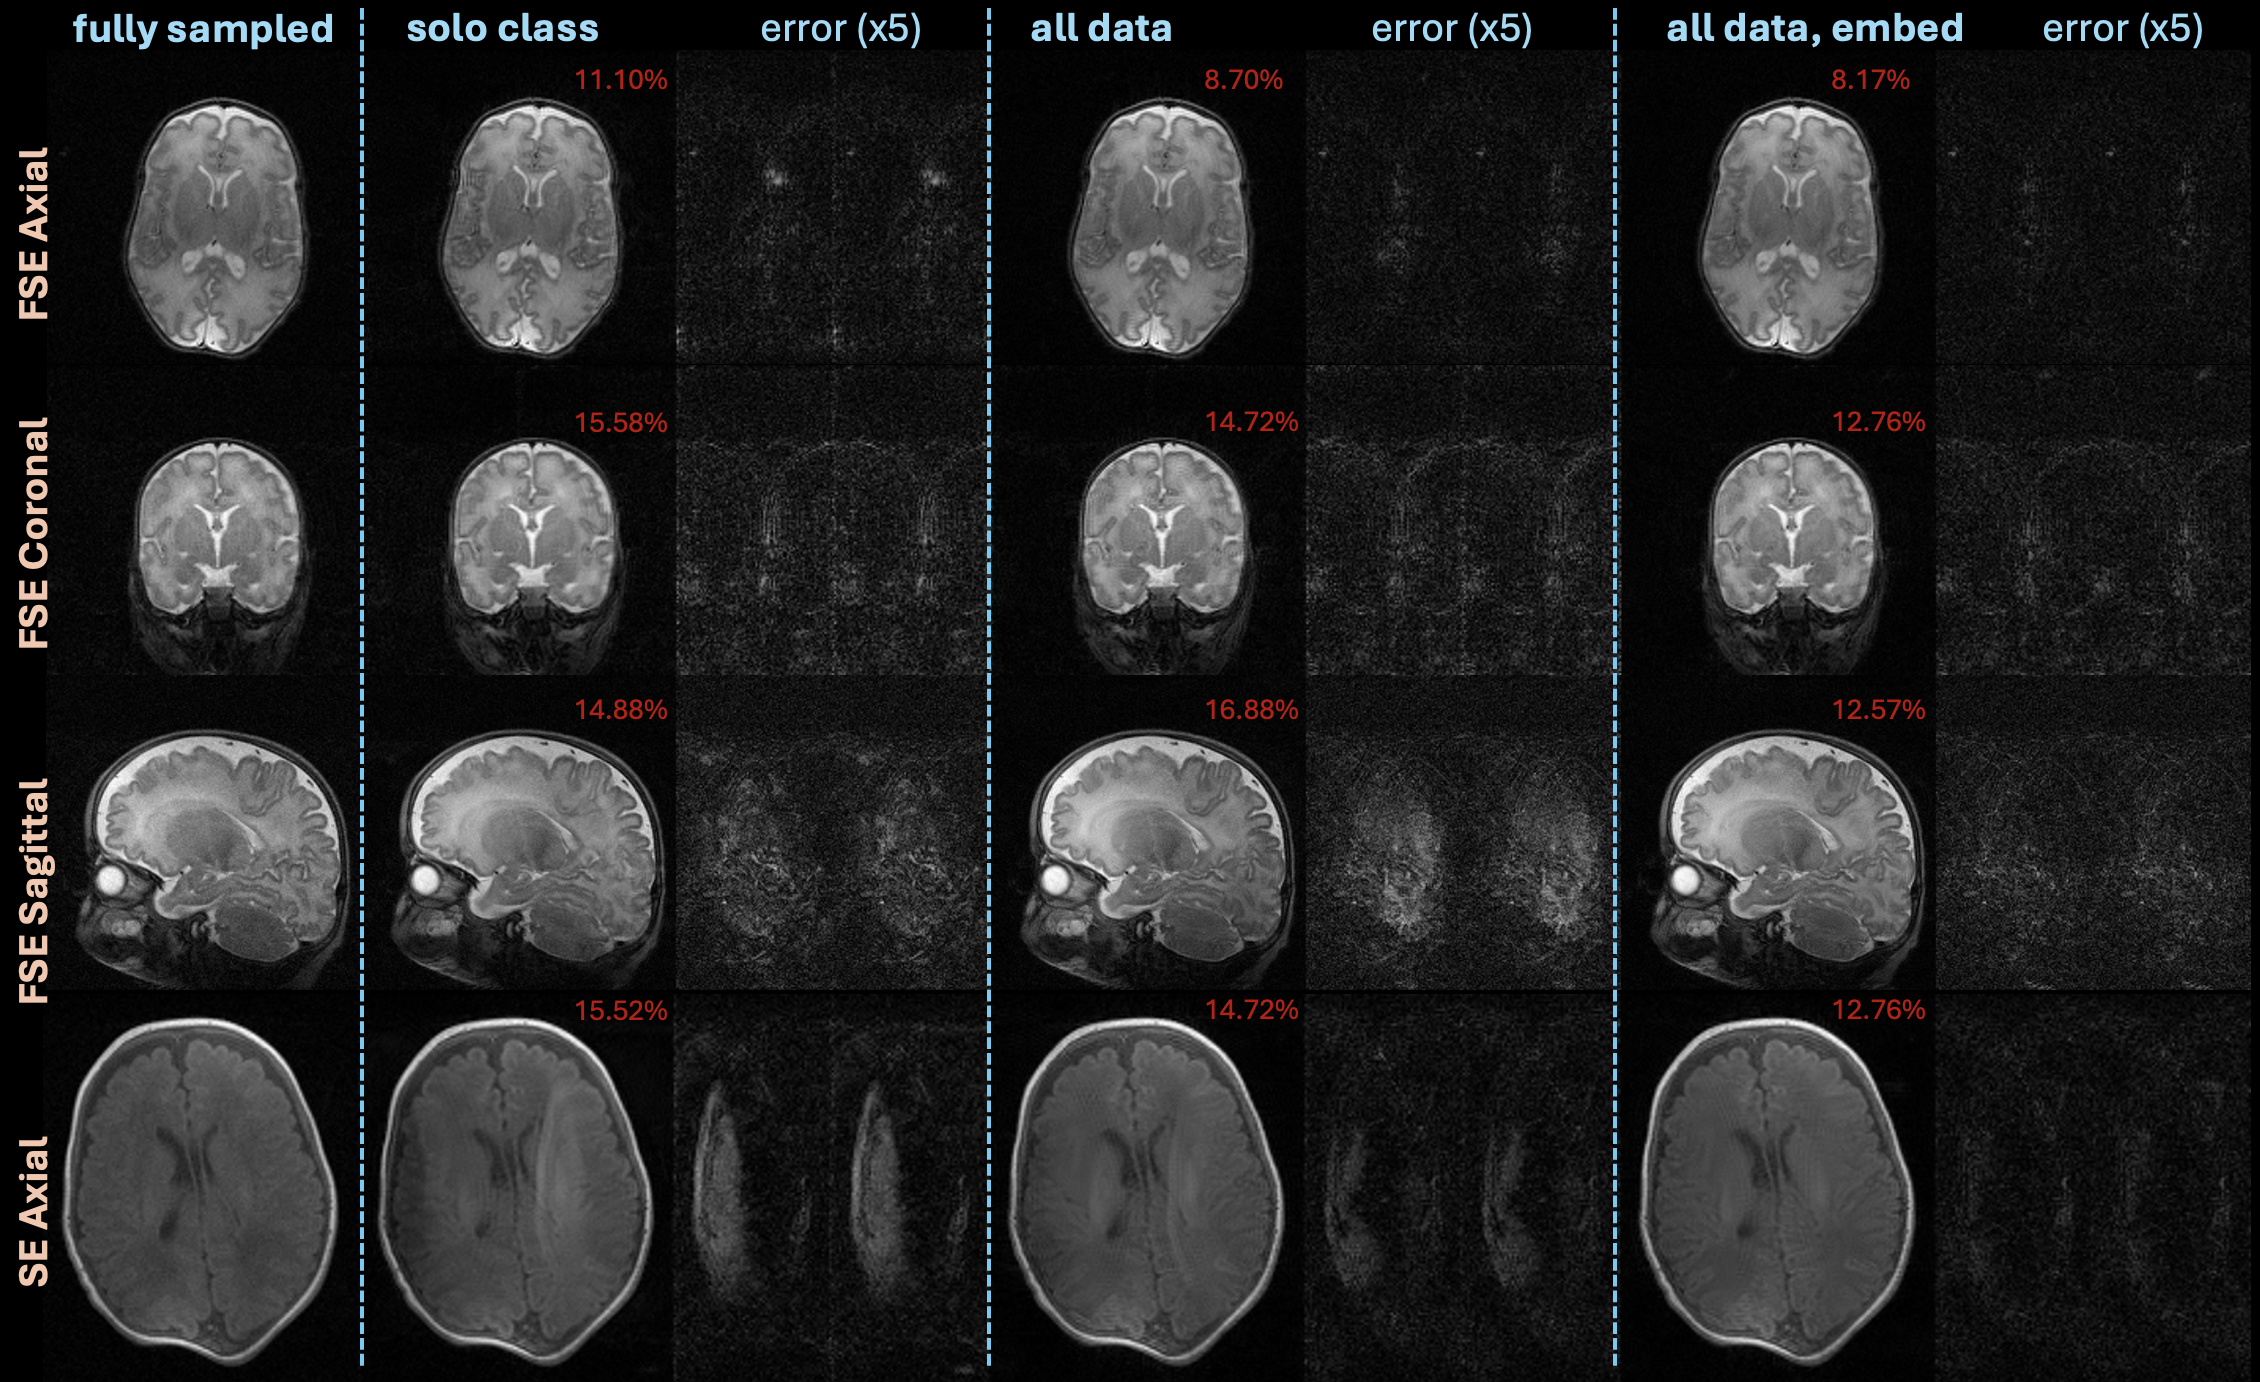

The violin plot in Figure 3 compares reconstructions of the different image classes with models trained separately on each image class, a model trained on all data without embedding, and a model trained on all data with embedding. Both models trained on all data achieve lower NRMSE across the dataset in comparison to the models trained separately. In addition, incorporating class embedding improves performance when training on all data. Figure 4 shows example reconstructions on all four image classes from this experiment. Similar to the overall quantitative setting, the model using all data with class embeddings achieves the lowest quantitative and qualitative error.

Figure 3: Violin plots comparing NRMSE of posterior sampling reconstructions on under-sampled data using diffusion models trained on just a single image class, trained on all data, and trained on all data with class embeddings. Results on all contrasts and orientations suggest that a diffusion model trained by combining all data with class embeddings yields the best quantitative performance.

Figure 4: Example images from the experiment comparing posterior sampling reconstructions on under-sampled data using diffusion models trained on just a single image class, trained on all data, and trained on all data with class embeddings. This is a specific illustration of the quantitative conclusion that using all data combined with class embeddings to train the diffusion model yields best performance.